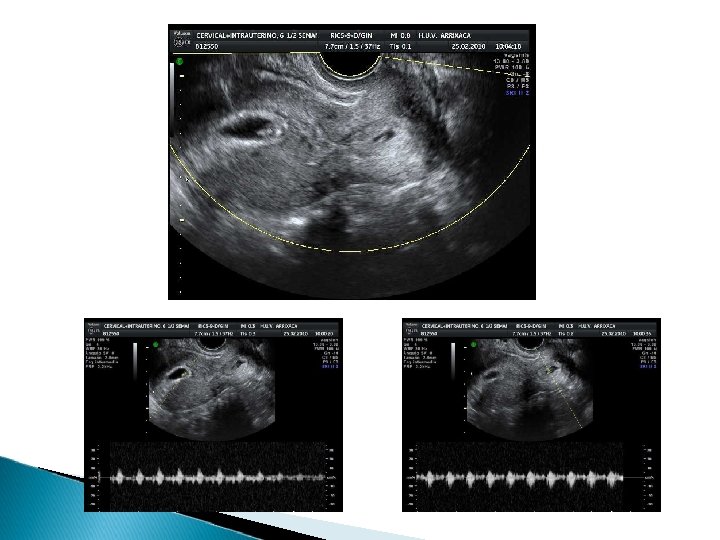

33 AÑOS AP: Fumadora de 20 cigarrillos al día AG: Eumenorreica. Con estudio de esterilidad normal AO: G 1 actual tras FIV con DGP por síndrome de MEN 2 A en el marido (con afectación suprarrenal y tiroidea). Se transfieren 2 embriones el 30/01/10

CASO CLÍNICO. Evolución. 25/2/10 Ingreso en reposo absoluto. Hb: 13, 4 g/dl. Tras informar a la paciente de la situación y ante un embarazo tan valioso se decide CONDUCTA EXPECTANTE. En los días sucesivos presenta metrorragia escasa-moderada de forma intermitente. 1/3/10 en eco de control se comprueba FC (-) en el embrión cervical. Ante la INTERRUPCIÓN DE LA GESTACIÓN CERVICAL se decide continuar con la actitud conservadora. 6/3/10 Se agudiza la metrorragia. Hb: 10, 8 g/dl. Se decide tomar una actitud activa. Se valoran las distintas posibilidades y la paciente decide la finalización de la gestación completa. Se plantea la realización de MTX INTRAARTERIAL + EMBOLIZACIÓN PROFILÁCTICA art. uterinas.

CASO CLÍNICO. Evolución. 12/3/10 Se transfunden (profilácticamente) 2 concentrados de hematíes por Hb de control en 8, 6 g/dl. ECO: Se mantienen ambos sacos. En el intrauterino FC (-). En los días sucesivos la paciente presenta una evolución satisfactoria, con ligeras molestias abdominales y spotting intermitente. La β- HCG satisfactoriamente. 29/3/10 ALTA control ambulatorio hasta β- HCG: 0 β- HCG: 43 UI/L ECO: GE de 10 mm. Con escasísimos restos. A nivel cervical, zona irregular hiperrefringente de 12 x 7 mm con escasos vasos sanguíneos.